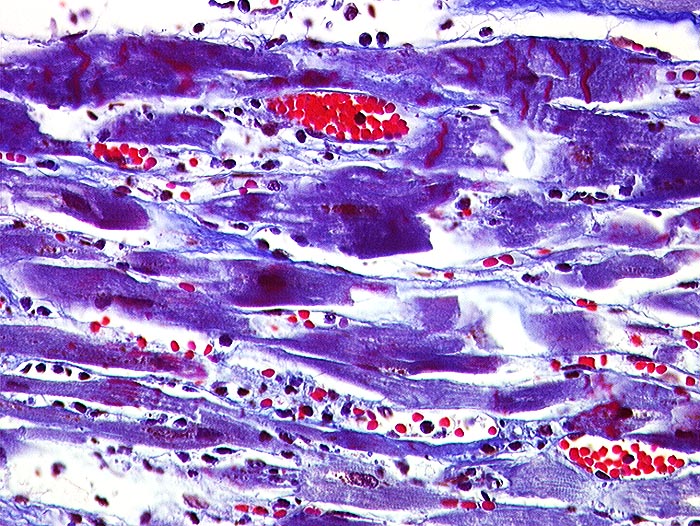

PathoPic – image database / PathoPic ID 815 - Akuter Myokardinfarkt: Kontraktionsbänder

Akuter Myokardinfarkt: Kontraktionsbänder

Quer zu den Myozyten verlaufende rot gefärbte Kontraktionsbänder. Granulozytäres Infiltrat rechts im Bild.

Paninfarkt bei schwer stenosierender Koronarsklerose mit Abgangstenose beider Hauptäste. Alter Verschluss der Arteria coronaria dextra.

Kontraktionsbänder sind nach 30 Minuten, zelluläre Infiltrate nach minimal 3 Stunden sichtbar. Kontraktionsbänder entstehen, wenn das hypoxisch geschädigte Myokard sich noch kontrahiert, aber nicht mehr relaxieren kann.